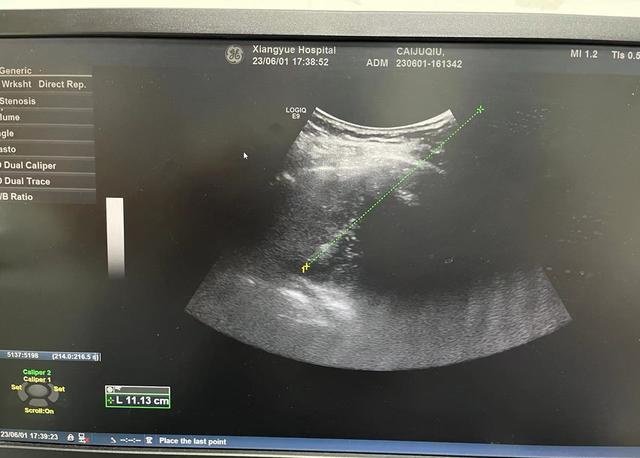

不幸的是,患者在治疗期间发现肝脏恶性肿瘤,由于此时患者因为严重的肝硬化,已不适合外科手术治疗,湖南省肿瘤医院常驻湖南省血吸虫病防治所湘岳医院的周慧俊教授马上与湖南省肿瘤医院专家进行远程会诊,经过MDT专家团队会诊,最终确定了肿瘤微创介入治疗的方案,决定先行肝动脉DSA造影确定肝脏占位病变的情况,再行肿瘤微波消融治疗。

李国文教授仔细分析了患者的病情,他表示:肝癌消融治疗是借助B超、CT等医学影像技术的引导,对肿瘤病灶靶向定位,局部采用物理或化学的方法直接杀灭肿瘤组织的一类治疗手段,具有对肝功能影响少、创伤小、疗效确切的特点,在一些早期肝癌患者中可以获得与手术切除相类似的疗效,尤其适合一些不能外科手术切除的患者。

该患者1个病灶贴近膈肌和肺部,另1个病灶紧邻右侧肾脏,手术难度和风险较大,经过术前周密准备、术中精准实施、术后严密观察,手术取得了成功,患者很快康复出院。